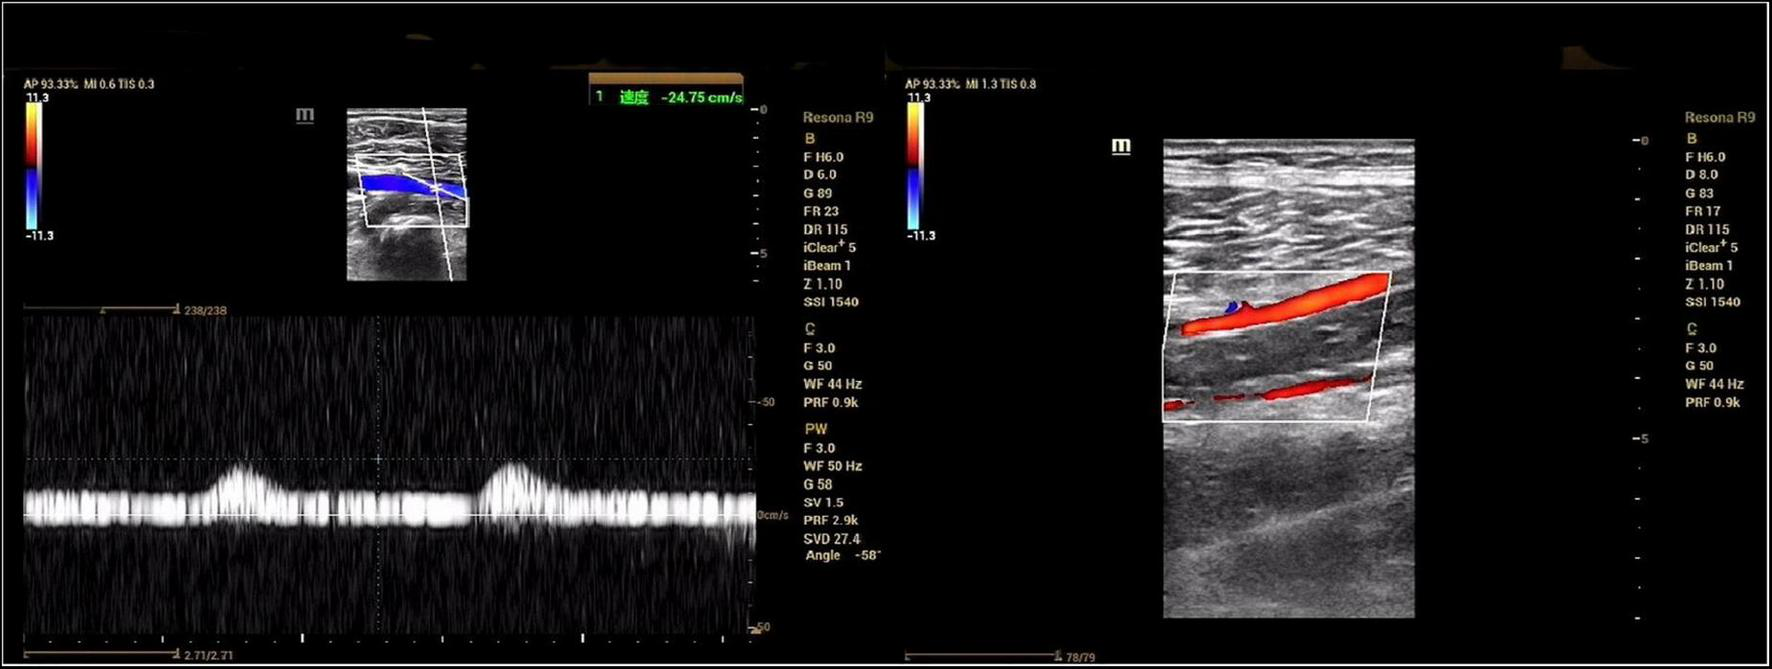

Ultrasound showed reduced flow velocity in the right lower limb artery, superficial femoral artery (34 cm/s), popliteal artery (24 cm/s), anterior tibial artery (20 cm/s), posterior tibial artery (17 cm/s), and peroneal artery (24 cm/s), with absent triphasic waves (Figure 1). CTA suggests severe stenosis and almost complete occlusion of the P1 segment of the popliteal artery (Figures 2A–C). MRI suggested that the popliteal artery was compressed by an oval cyst with high signal intensity on T2-weighted, which is 1.7*2.5*3.1 cm in volume (Figures 2D–G). A diagnosis of popliteal artery entrapment syndrome is proposed.

FIGURE 1

Preoperative ultrasonography. The spectral pattern was changed and triphasic waves were absent.